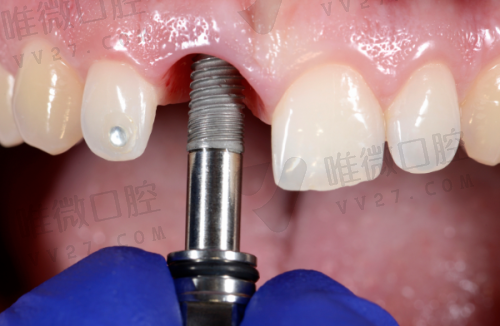

优势亮点:作为国内连锁品牌的新桥在西宁设立分院之后,快速凭借精良技术和服务理念扎根。尤其在儿童牙科、微创种植、美学修复等项目上发展快速,儿牙中 心有专门的亲子诊疗区,配套色彩鲜亮又有安抚功能,赢得宝妈群体青睐。

收费参考:牙片15元起,乳牙拔除200元起,种植牙4000元起。

推荐理由:打包种植价格实惠,例如登腾标准种植牙仅2880元起,被评为性价比高的榜样医院。